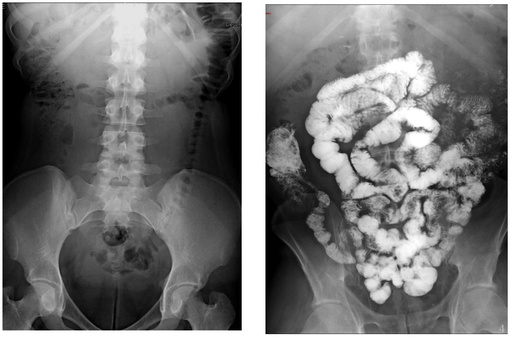

Cas cliniques - Secteur Abdomen

Cancers colo-rectaux

Contraste digestif en radiologie adulte